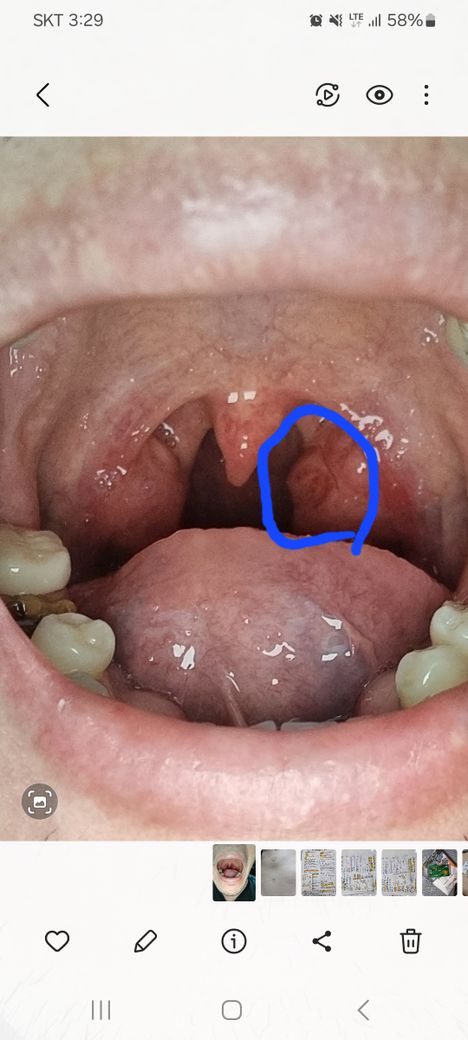

편도가 큰편이라고 하던데 편도에 저런 빨갛게 상처가 있는데 정상인가요

우연히 보다가 편도에 저렇게 빨갛게상처(?)처럼 보이는걸 발견했는데 정상인가요? ㅜㅜ

올려주신 사진으로 미루어 편도가 정상보다 큰 것 외 특별한 이상 소견은 관찰되지 않습니다.

편도가 크다해서 반드시 수술이 필요한 것은 아니지만 편도 비대로 인하여 수면 무호흡증이 생기거나 1년에 3회 이상 편도염이 반복되는 경우라면 수술적 제거의 고려가 필요하겠습니다.